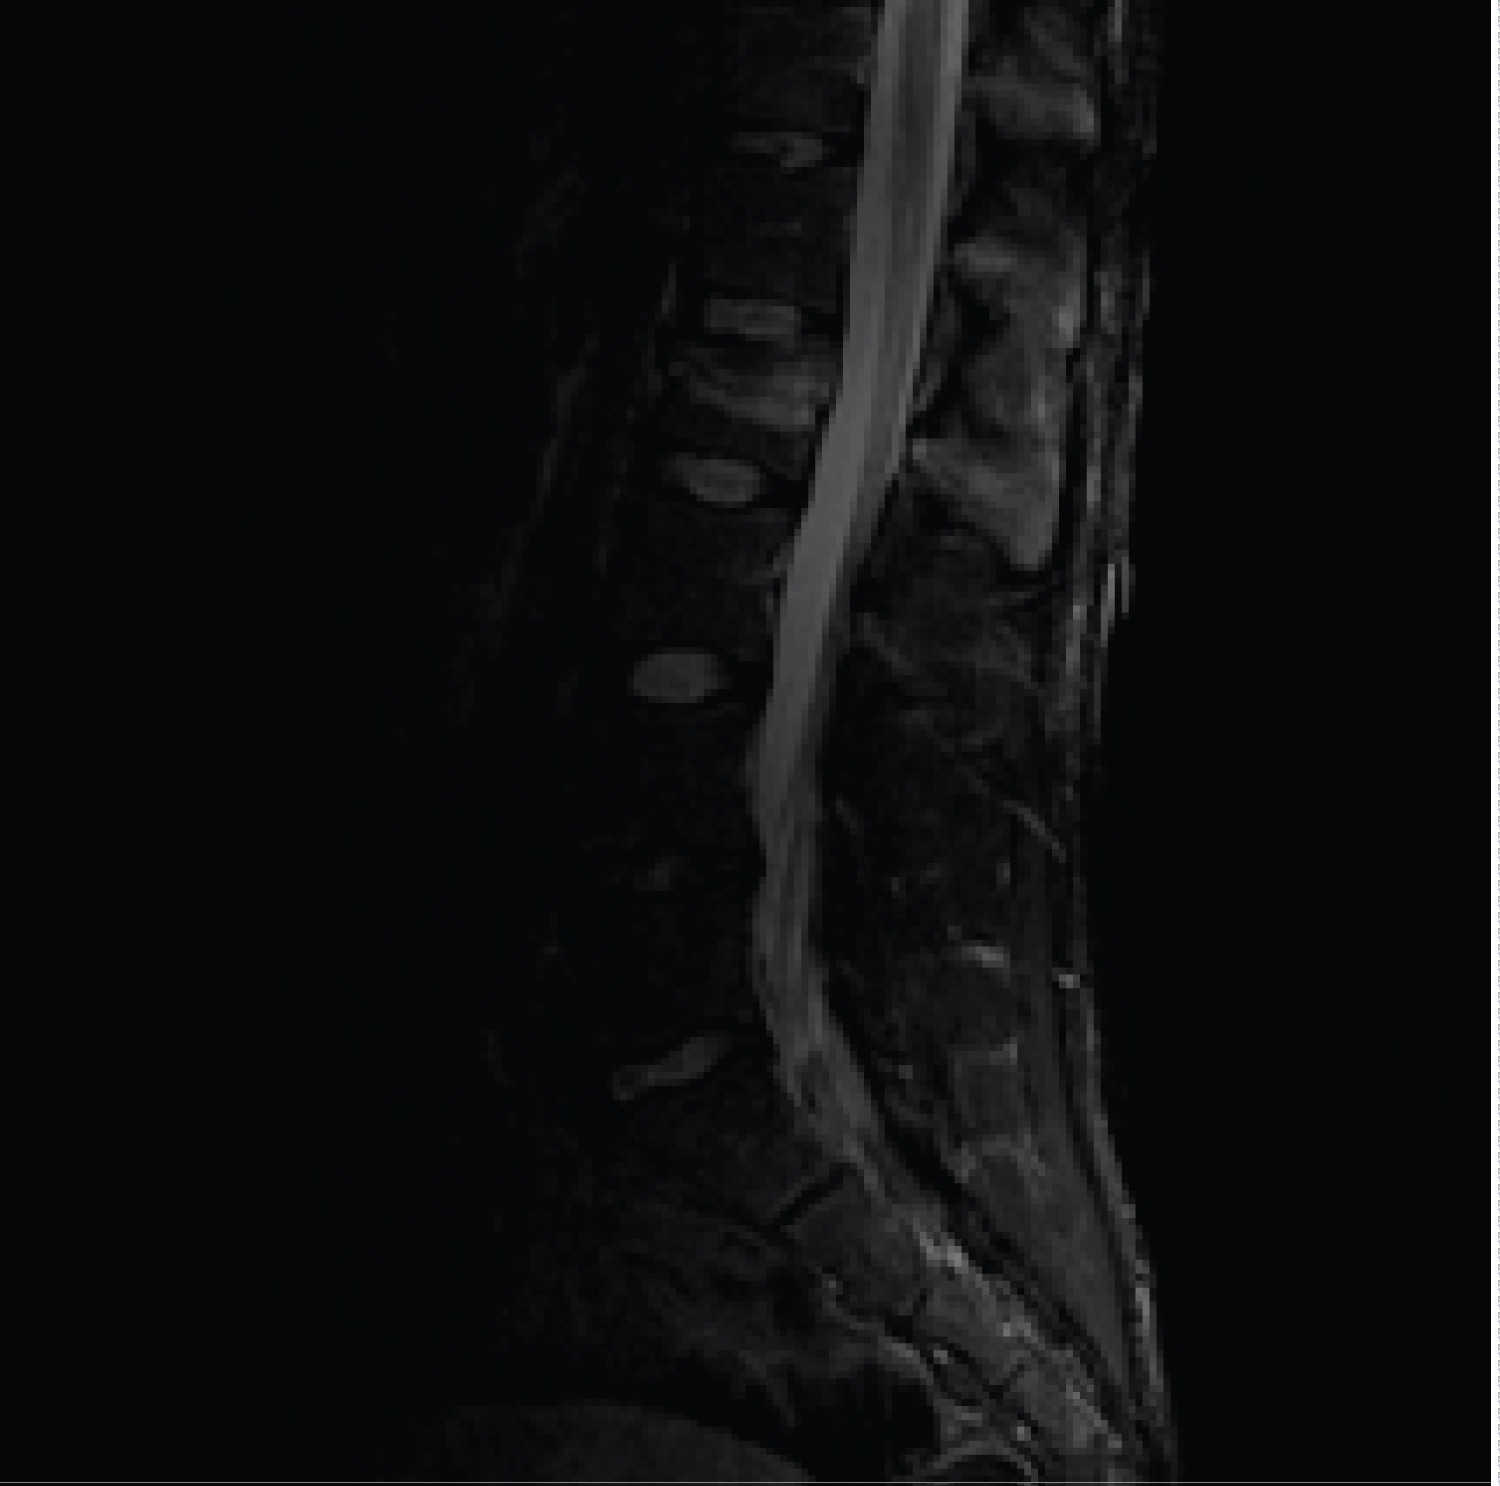

After carrying out the anamnesis, and observing the mechanism of production in the Video 1, we suspect a type B fracture, so a MRI was performed, where the lesion of the posterior ligament complex was confirmed, being then diagnosed as type B2 fracture of AO Spine, performing then the timely surgical treatment (Figure 3, Figure 4 and Figure 5).

Figure 4: Fracture L2 level (a) Sagittal MRI image completely rupture of the posterior ligamentary complex was evaluated. View Figure 4

Spinal support ligaments include the ligament anterior longitudinal, posterior longitudinal ligament, interspinous and supraspinatus ligament. These ligaments are identified in sagittal images as linear areas of low signal strength. The interruption of this hyposignal constitutes direct evidence of ligamentous disruption and can be identified in any pulse sequence In case of ligament injury interspinous we can observe areas of increase signal in T2 sequences in interspinous soft tissues [5].